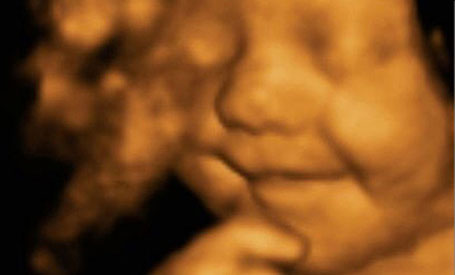

Leo David Hargreaves hiện đã 5 tháng tuổi. Nhưng điều kì diệu là ngay từ khi còn nằm trong bụng mẹ, nụ cười đã luôn thường trực trên môi cậu bé này.

Leo David Hargreaves mỉm cười khi còn trong bụng mẹ.

Khi mẹ của Leo, chị Amy Cregg (24 tuổi) ở Accrington, Lancashire (Anh), mang thai cậu bé được 31 tuần, trong một lần đi siêu âm, hình ảnh thai nhi đang mỉm cười trong bụng khiến chị và bác sĩ siêu âm vô cùng ngạc nhiên.

Phát ngôn viên của Bệnh viện Babybond, nơi chị Cregg siêu âm thai, cho biết: “Cả Amy và chúng tôi đều vô cùng ngạc nhiên trong suốt quá trình siêu âm. Tôi nghĩ rằng con của Amy là một em bé tuyệt vời với “nụ cười chiến thắng” luôn nở trên môi”.

Chị Cregg nói rằng bé Leo luôn nở nụ cười trên môi ngay khi còn nằm trong bụng mẹ cho đến lúc cậu bé được sinh ra (ngày 30/6/2014) và cho đến bây giờ cũng vậy.

Nụ cười "quyến rũ" của Leo từ khi còn trong bụng mẹ đến thời điểm hiện tại.